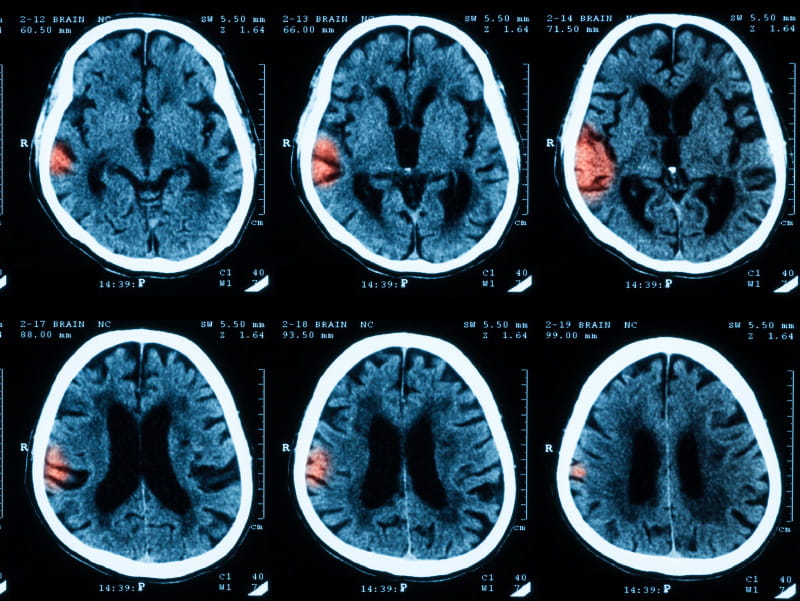

After a stroke, women are known to have a worse health-related quality of life than men, both in the short term and long term. Now a study gives some insight into why, and what can be done to alter the aftermath.

The findings, published Thursday in the journal Stroke, suggest women have a lower post-stroke quality of life because they are older at the time of a stroke, have more severe strokes, are in worse health beforehand, and are more likely to develop depression afterward. Quality of life measures included mobility, self-care, independent living, psychological well-being and social relationships.